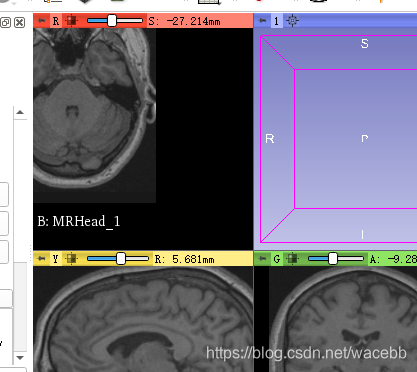

接下来我们学习如何剪裁。

首先我们要选择volume rendering 模块,同时界面发生变化。

在此位置,可以选择你想做出修改的文件:![]()

当我们点击

这个小眼睛的时候,3D数据就会显示出来了:

我们可以使用

使图像处于画面中心位置。

我们在左边present 选择想显示的部分,比如骨头啊,神经什么的:

比如我选择了ct-bone:

我们也可以通过

shift调整显示。